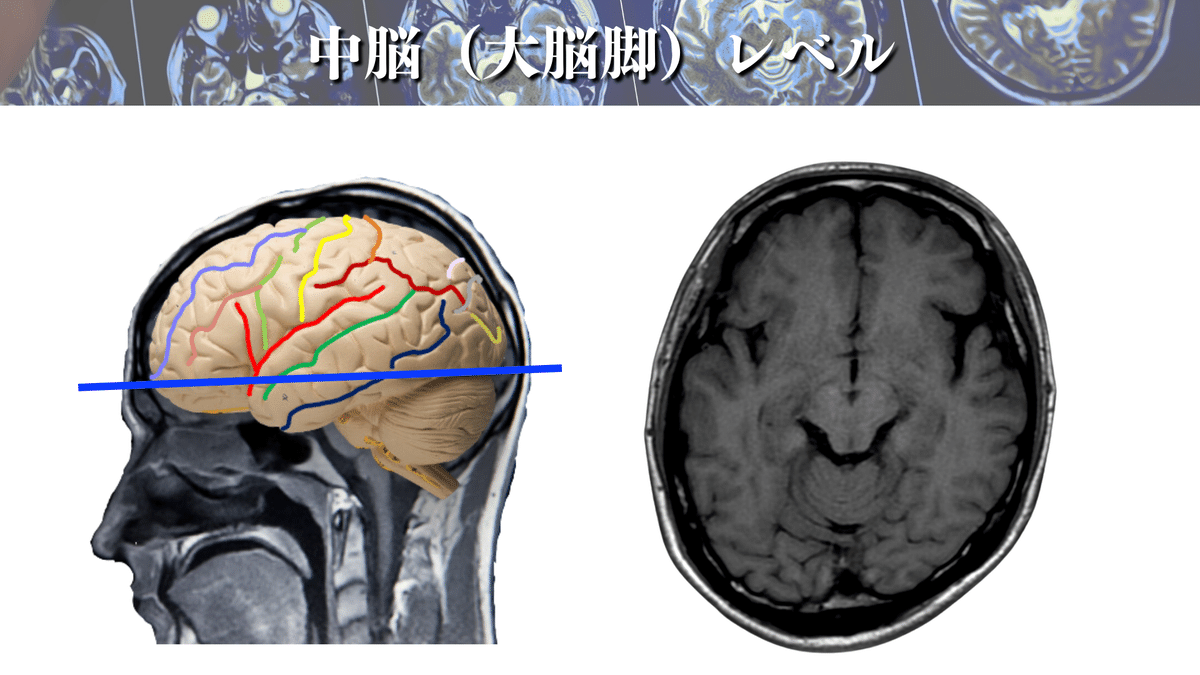

中脳(大脳脚)レベル

脳幹の初めは中脳レベルになります!

ちなみに脳幹レベルになると構造が複雑かつ、小さくなりますので、MRIだけでの同定はめちゃくちゃ至難の業です、、、😱

さて、本題に戻りまして、解像度を上げてみるとこんな感じです!